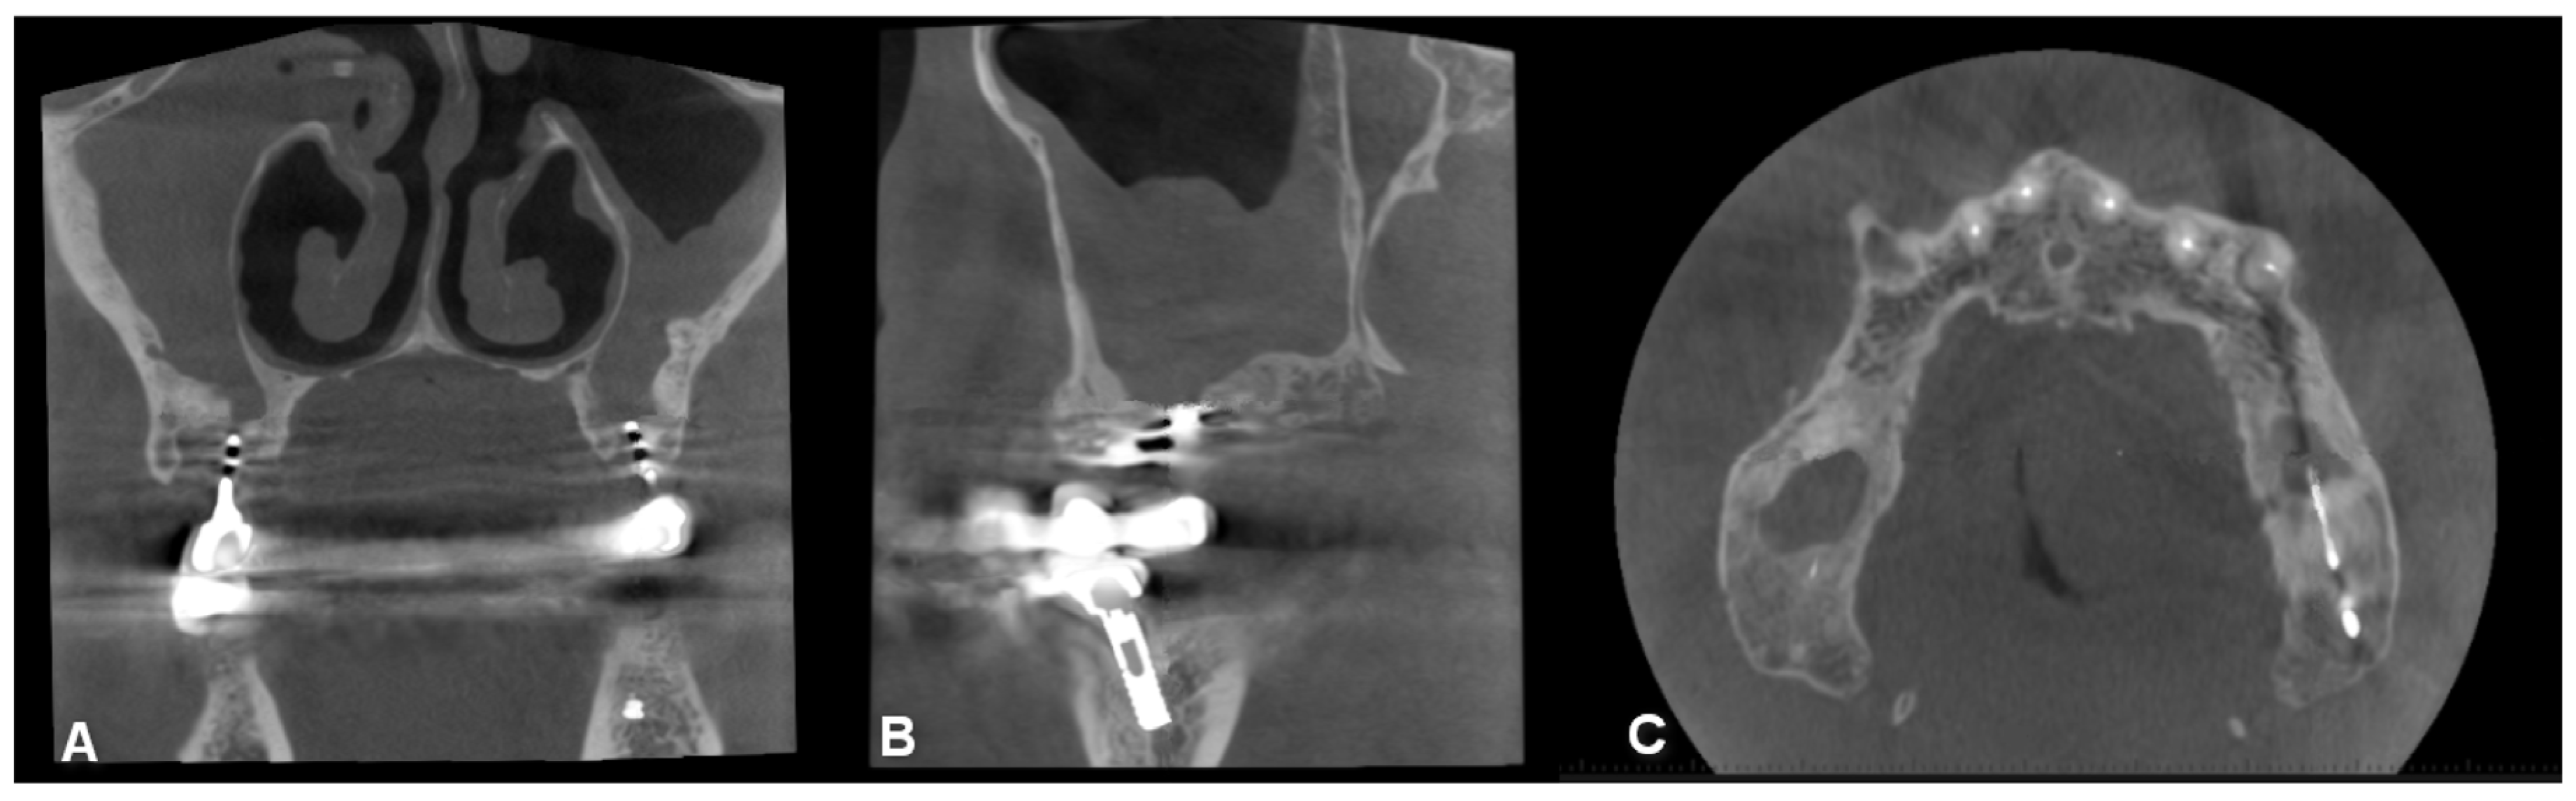

Figure 6. CBCT image of unilateral maxillary sinusitis and oro-antral fistula with the characteristic radiological image of fungal infection, which radiologically mimics foreign bodies ((A): coronal, (B): axial, (C): sagittal view).

Jpm 13 01291 g006